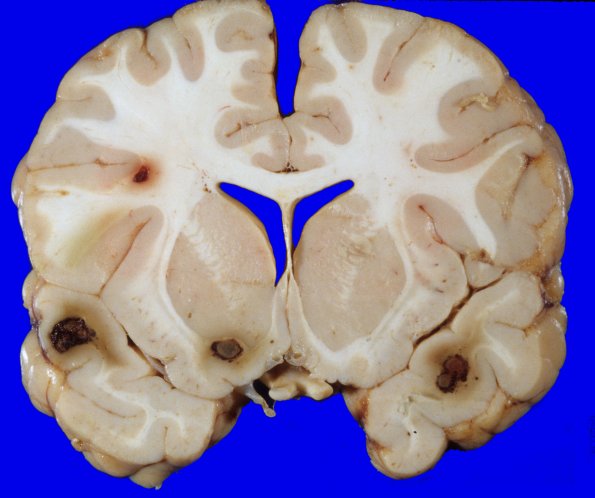

Leukemic nodules have a distinctive appearance of gray masses surrounded by a rim of admixed hemorrhage located at the gray/white junction with surrounding edema.